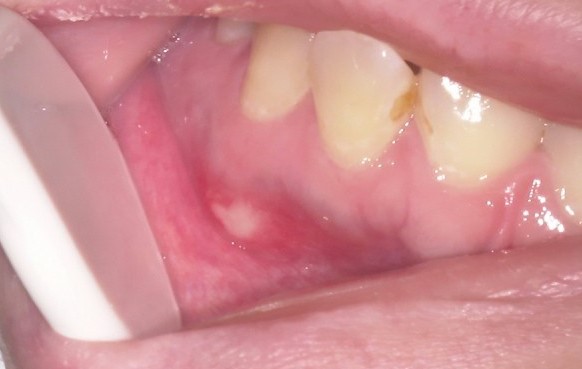

口内炎の治療するなら

口内炎みんななることおおいですよね。意外に治りが悪くてきなってしまうことが多いと思います。 そんなときどうするか?それを今日は解説していこうかなと思っています。 口内炎できたらまずは触らない!それにかぎります。 かさぶた […]